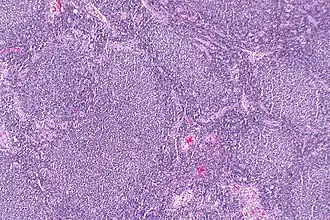

Biopt van folliculair lymfoom (H&E-kleuring)

Het folliculair lymfoom (FL) is een indolent/laaggradig non-hodgkinlymfoom (lymfeklierkanker). Het lymfoom ontstaat door een ongeremde celdeling tijdens de uitrijping van B-lymfocyten uit het kiemcentrum in de follikel van de lymfeknoop en volgt een (deels) cirkelvormig patroon.

Diagnose vindt altijd plaats middels een beenmergonderzoek en een lymfeklierextirpatie of het nemen van een biopt uit het aangedane weefsel. Ann Arbor-stadiëring wordt gebruikt om het stadium van de ziekte te bepalen.